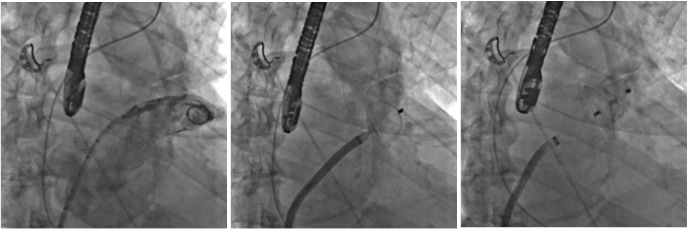

ICPS(写真1)という施設はパリ郊外のMassyという所にあるcardiology、特にinterventionがメインの病院で、年間1万件ほどのCAGおよび2000件前後のPCIを施行しているhigh volume centerです。またcoronary interventionだけでなく、TAVI、MitraClip、LAA閉鎖術(写真2)といったstructural heart disease (SHD)に対するinterventionもさかんに行われております。特にaortic stenosis (AS) に対するTAVIに関しては、週5〜6件、年間200件以上の症例を施行しており、Edwards SapienXTやCoreValveといった第1世代でバイスだけでなく、Edwards Sapien3(写真3)やLotus valveといった第2世代デバイスも積極的に使用している施設です。

Arai1-3

写真3